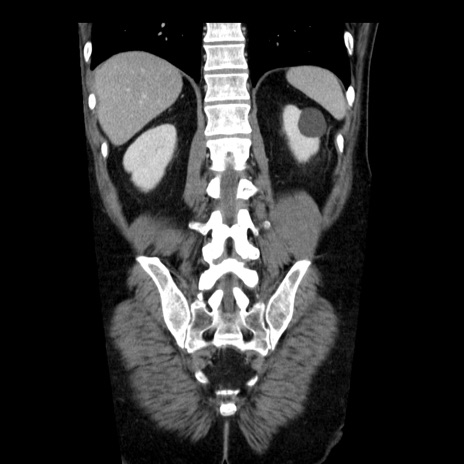

症例29(冠状断像)

【症例】40歳代男性

【現病歴】2日前から胃痛あり。徐々に周期的な激痛に変化した。本日になっても激痛があるため受診。

【身体所見】意識清明、BT 38-39℃台あり、腹部:膨満、やや硬、右下腹部に圧痛あり。

【データ】WBC 8500、CRP 23.26